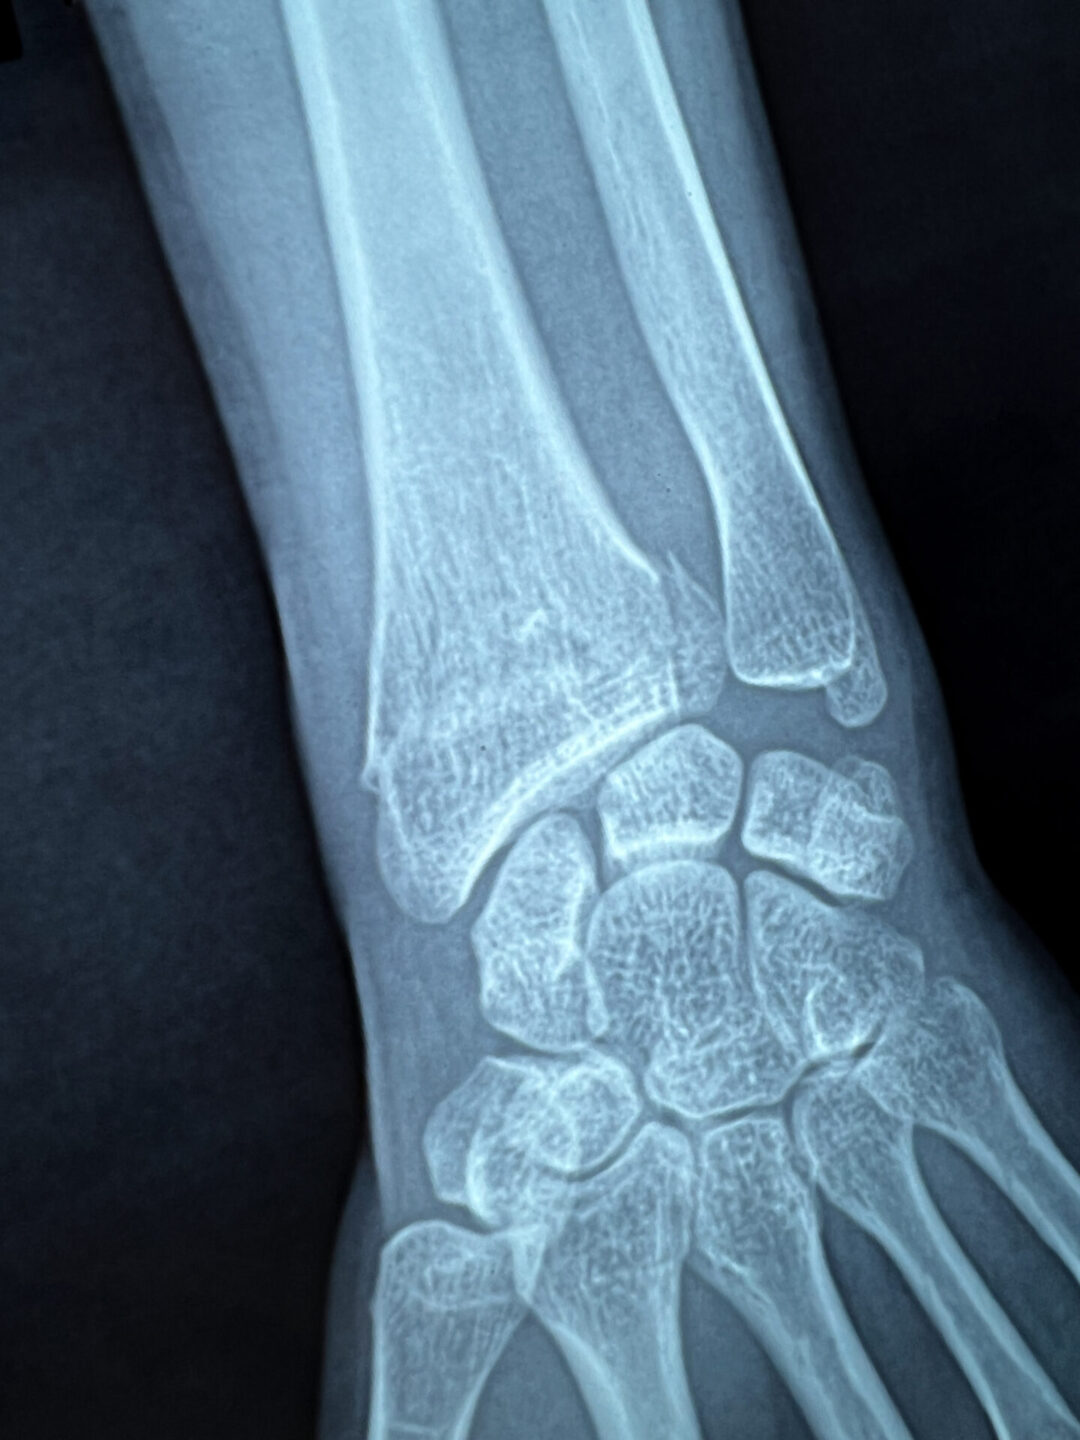

The doctor now speaks through Google Translate on his phone instead of via Mr. Trung, whose translation skills had hit their limit. My verdict: a broken wrist, possibly requiring surgery. The weight of this information, as revealed in a short sentence on an iPhone screen, as well as the uncertainty of my trip, potential surgery, and future plans hit me like a ton of bricks. This time, I can’t stop the tears that come.

I FaceTime my friend, Kate, who luckily for me, is amazing in these types of scenarios. Recalling an Orthopedic surgeon I saw back home a year ago, I suggest, “If I can get him my X-rays, he can advise on surgery and if can continue my trip—I’m still his patient after all.” While FaceTiming me from her computer, Kate calls my doctor’s office and I explain the situation remotely. The receptionist relays that I must email the details quickly so my doctor could review during the few hours he’d be in office the next morning before their week-long New Year’s closure. Over the next 45 minutes, Kate helps me type up my injury details, and I forward her X-rays and wrist photos. Together, though thousands of miles apart, we send the email.

My doctor’s reply came in a little over 24 hours later, while I was exploring Hoi An: “Based on your x-rays, this is a non-op fracture and it is ok to complete your trip in a splint“.